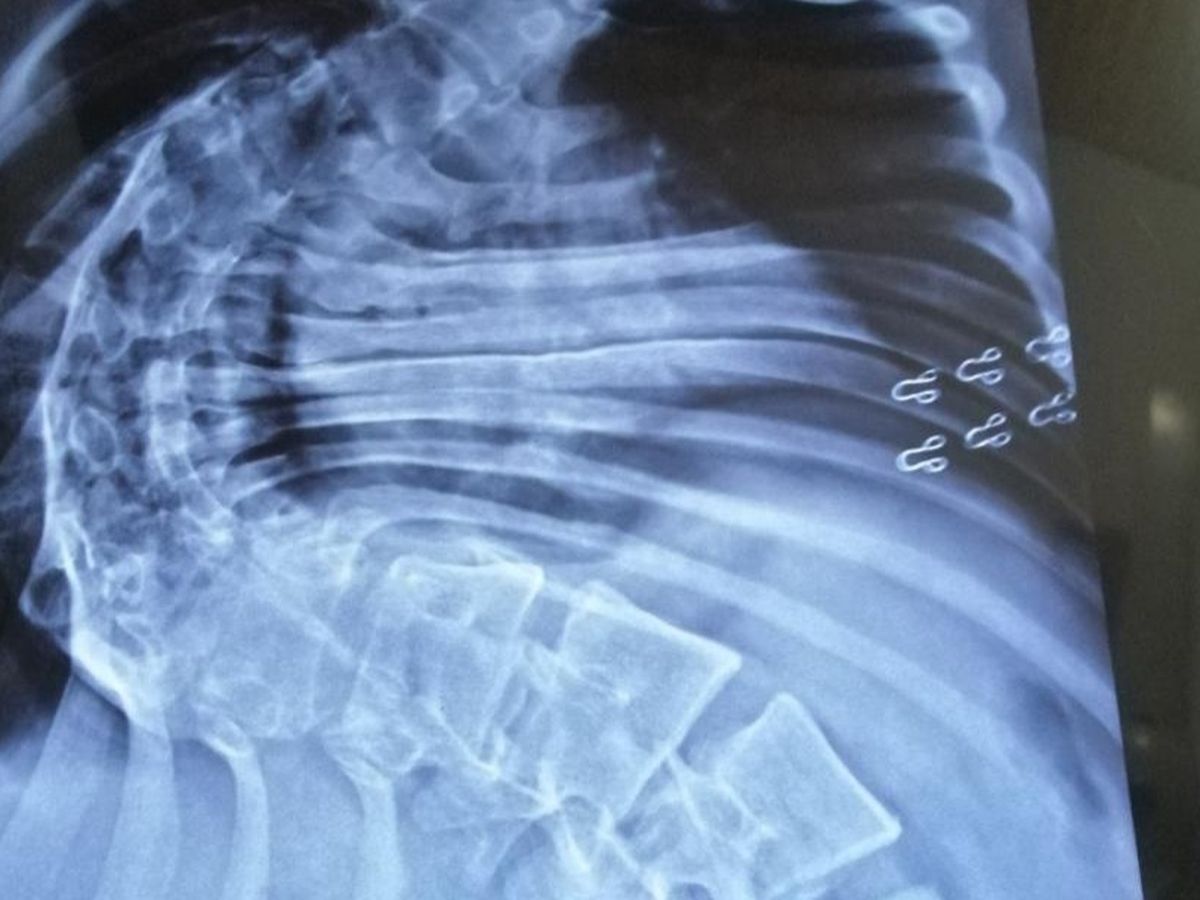

I went to an orthopedic in Islamabad. Only an X-ray determined the nature of my spinal curve. He recommended MRI's for further diagnosis. These MRI's cleared that my kidneys have been deformed and my lungs and heart are under great compression. This situation could be life threatening to me. For the pain management he prescribed me heavy pain killers which I have to take 3 times a day. My kidneys are getting badly affected from this medication. I am also unable to got out or socialize due to this pain, so this thing is causing me depression as well. My respiratory system is also under a lot of compression due to my curved spine which causes shortness of breath.

For the meantime those pain killers helped me to get rid of this pain and I started working as a freelancer to support myself financially. Things were better until I started experiencing a severe pain & fatigue again due to long sitting hours. My curve got even worse with the cob angle of 100+ degrees and I left the job. This state of affairs effectively means that my life has come to a standstill.